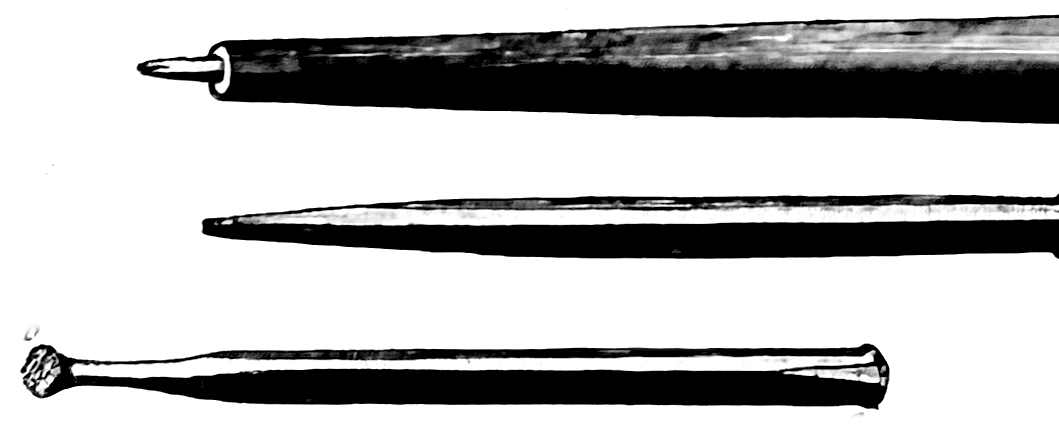

I also took to twisting medieval-looking steel massage rods and harrows into the muscles of my legs to soothe them at night, but the pain continued, and I lost sleep and weight. A round of acupuncture gave almost a day of blessed relief; £38 for half an hour’s pin-work on Lower Clapton Road. When my wife led me down to Homerton A&E one Saturday afternoon, an intern concluded that pain alone did not warrant further investigation: we could go home.

On being rushed to the Royal London for an operation to seal the aneurysm with platinum coils, it seems that the moment the equipment entered my brain (inserted by way of the veins in the leg, with a camera threading the coils, winding its way through your heart before landing at the center of the brain to do its job: a “GDC coiling of anterior communicating artery aneurysm”), my brain simply shut down in a vasospasm, cutting off the blood to the brain. The operation was stopped immediately, and I was returned to the Intensive Care Unit, where my family was told to expect my death at any moment, or, short of that, for me to emerge as paraplegic.